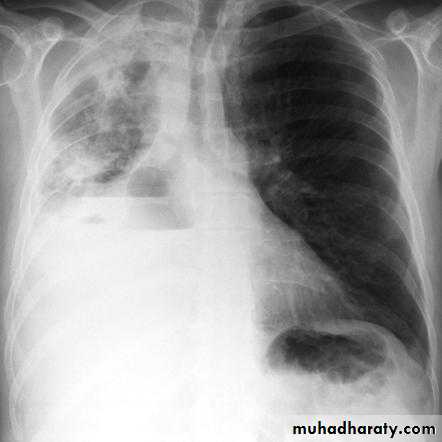

Left side massive pleural effusion with mediastinal

shift2-Ultrasonography is more accurate than plain chest radiography at determining the volume of pleural fluid. facilitates safe needle aspiration and guides pleural biopsy. may also distinguish pleural fluid from pleural thickening.